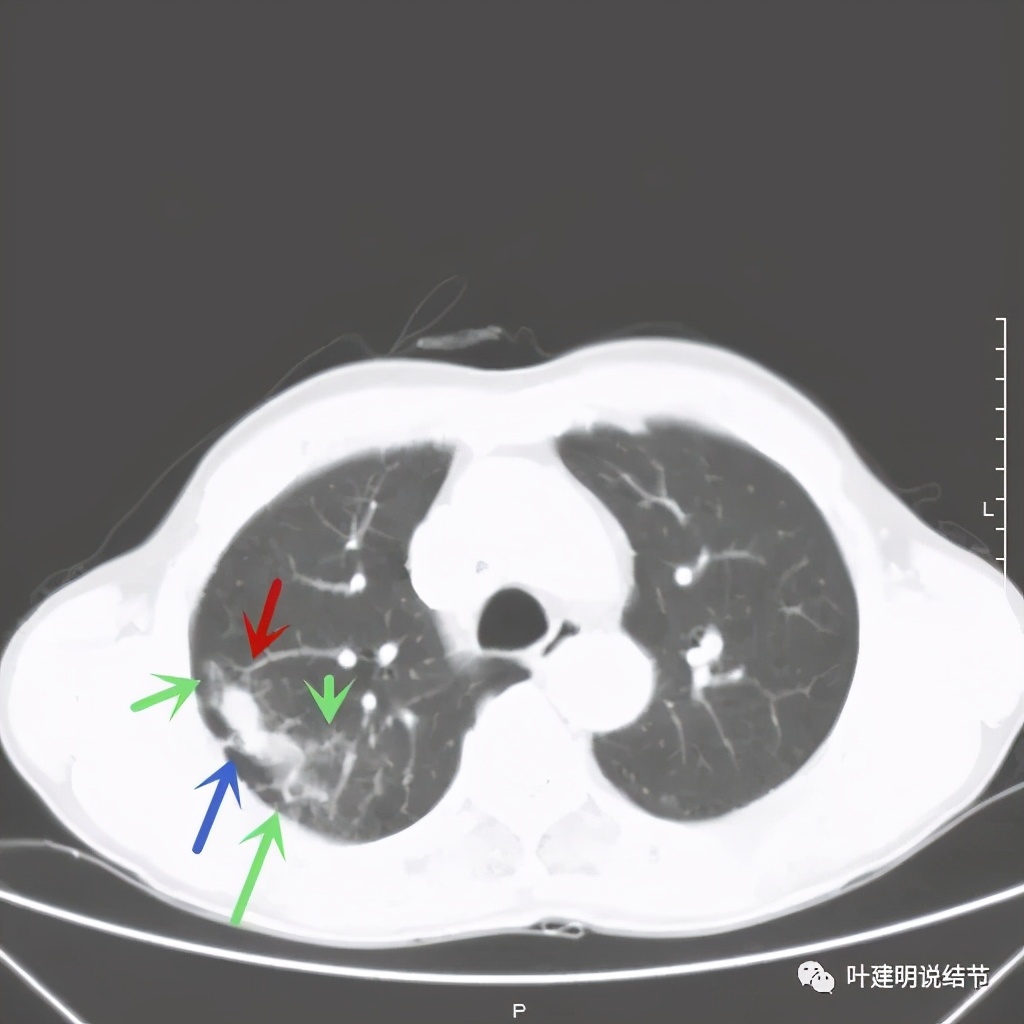

金华的某A,今年66岁,前几天在当地医院查胸部CT平扫发现右上肺占位,当时来找我看时,我想首先肺内占位是要警惕肺癌的,建议其住院进一步做增强CT,以及完善其他相关检查。其中增强CT报告示:右上叶约7*6厘米的肿块,增强后显著强化。而且某A曾于2018年5月在本院做过肺部CT,当时右上肺没有病灶的。我们先来看这次的CT图像:

红色示病灶,绿色示病灶旁边有磨玻璃成分,但较为模糊;蓝色箭头示病灶与胸膜间有牵拉,但力度不太够。

总体上感觉,病灶比较大,不规则,不是圆形或圆形生长,周围有模糊磨玻璃影(考虑炎性渗出性?),虽有胸膜牵拉,但力度不够;增强有显著强化。病灶明显却无明显临床症状,普通感染是不像的,要么是结核,要么是肺癌。但肺癌的话,在2年前没有,2年内长到这么大,恶性程度应该很高,但其纵隔淋巴结却没有明显肿大。而且病灶的边缘部分过于光滑,没有见到肿瘤的细毛刺,膨胀性也不够。整体看病灶有点像“腰子”形,弯弯曲曲的。所以我的感觉更倾向结核性。查了肿瘤筛查指标如下: